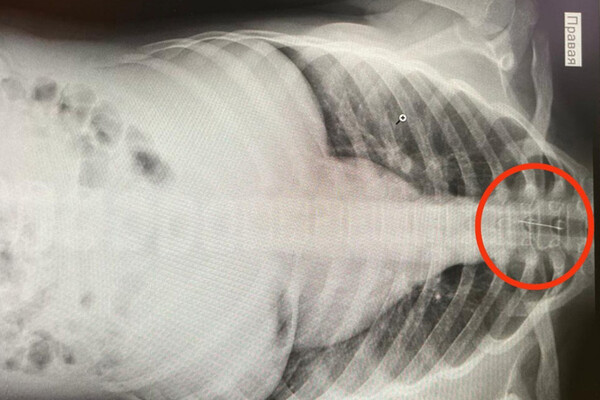

В Башкирии врачи Баймакской ЦРБ и Республиканской детской клинической больницы в Уфе помогли 14-летней школьнице, которая случайно вдохнула швейную иглу. Об этом рассказал главный врач Баймакской больницы Ильшат Рыскужин на своей странице во «ВКонтакте».

Подросток жаловалась на боль в груди, кашель и обильное слюноотделение. Обследование показало наличие инородного тела в трахее. После консультации с коллегами из республиканской больницы девочку на скорой перевезли в Уфу.

Там специалисты РДКБ применили метод бронхоскопии, позволивший аккуратно удалить иглу из трахеи, исключив серьезные последствия.